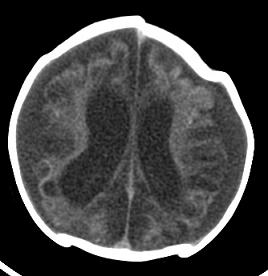

男,4个月大,2个月前无诱因下四肢抽搐、伴呕吐,近2天来抽搐频发,伴发热。查体:双眼疑视,神萎、纳差;颈抵抗,四肢张力高。

病史太长了,原因不好定,不过如果2个月前小儿正常的话可考虑积水型无脑畸形,积水型无脑畸形小儿刚生下来表现可正常,存活一两个月后出现症状.

另不除外缺血缺氧性脑病,感染等改变

2个月前缺血缺氧性脑病留下的后遗症。

脑出血后,软化灶形成了。脑发育不良

支持缺血缺氧性脑病留下的后遗改变(脑软化灶+脑发育不全+双侧慢性硬膜下积液+小头畸形)。

支持考虑缺血缺氧性脑病留下的后遗改变。

要注意化脓性脑膜、脑炎,硬膜下积脓,脑积水的可能,建议腰穿助诊。